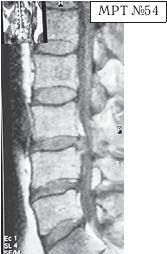

На МРТ № 53 — поясничный отдел позвоночника. На данном «контрольном» снимке, после устранения методом вертеброревитологии секвестрированной грыжи межпозвонкового диска в сегменте LV-SI, наблюдаются остаточные явления дегенеративного процесса. Но в целом состояние поясничного отдела позвоночника, отображённое на этом снимке, довольно хорошее, поэтому будем использовать его для сравнения как вариант нормы.

На МРТ № 54 наблюдается изменение физиологического лордоза, стеноз спинномозгового канала, грыжа межпозвонкового диска и спондилёз в сегменте LIII-LIV, ретроспондилолистез — LIV и LV. Как правило, причина вышеупомянутых болей при таких патологиях скрывается в дугоотростчатых суставах. Дело в том, что при изменении физиологического лордоза извращается «работа» и дугоотростчатых суставов. В состоянии нормы дугоотростчатые суставы имеют дугообразную форму и расположены во фронтальной, горизонтальной и сагиттальной плоскостях в среднем под углом 45о. При развитии дегенеративнодистрофического процесса в межпозвонковом диске (снижении высоты диска, возникновении сегментарной нестабильности) происходит смещение суставных поверхностей дугоотростчатых суставов по отношению друг к другу, что в свою очередь приводит к уплощению физиологического лордоза и его кифозированию (МРТ № 55) или же формированию гиперлордоза (МРТ № 56). И в том, и в другом случае данные процессы, как правило, сопровождаются сдавлением спинномозговых корешков (что вызывает соответствующие боли). Кроме того, сами дугоотростчатые суставы хорошо иннервированы, поэтому протекание патологических процессов, с участием этих суставов, сопровождается соответствующими болевыми ощущениями. ![]() На МРТ № 55 наблюдается уплощение физиологического лордоза в поясничном отделе позвоночника. На МРТ № 56 наблюдается гиперлордоз в поясничном отделе позвоночника. На МРТ № 57 наблюдаются нарушения конгруэнтности в дугоотростчатых суставах в сегменте LV—SI (указано стрелкой) вследствие гиперлордоза. ![]() |